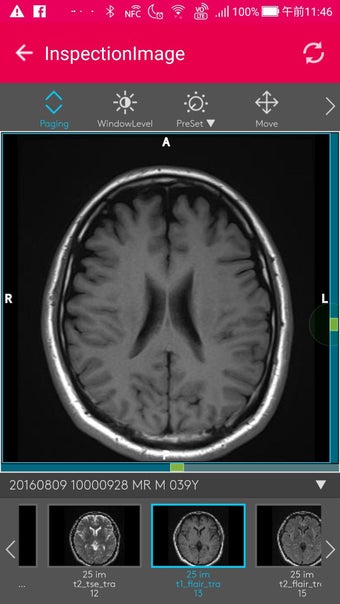

MySOS เป็นแอปพลิเคชันบนมือถือที่ช่วยให้ผู้ใช้เข้าถึงข้อมูลและบริการที่เกี่ยวข้องกับสุขภาพและการดูแลรักษาสุขภาพในประเทศญี่ปุ่น มันถูกออกแบบมาเพื่อให้การช่วยเหลือในกรณีฉุกเฉินทางการแพทย์และรองรับการดูแลสุขภาพและการบริการฉุกเฉิน

เมื่อคุณใช้ MySOS คุณสามารถเข้าถึงข้อมูลและบริการที่เกี่ยวข้องกับสุขภาพและการดูแลรักษาสุขภาพในประเทศญี่ปุ่นได้ คุณสามารถส่งคำขอความช่วยเหลือไปยังผู้ที่คุณไว้วางใจ เช่นครอบครัวหรือเพื่อนของคุณ คุณยังสามารถยืนยันตำแหน่งของ AED หรือโรงพยาบาลที่คุณต้องการไปเยี่ยมชมและส่งคำขอความช่วยเหลือไปยังผู้ที่คุณไว้วางใจได้